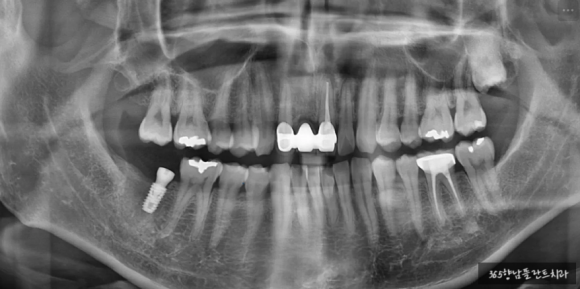

24.04.12 / 발치 후 약 1개월 경과 시점

상실된 어금니는 여건이 가능하다면 발치와 동시에 수술을 진행해서 회복 기간을 단축하고 있지만, 불가능한 때도 있는데 그중 하나가 치조골 잔존량이 적고 신경.관과 가까운 경우입니다.

요즘은 과거에 비해 짧은 임플란트(길이 4~5mm)여도 장기적으로 잘 고정되지만, 초기에 임플란트 고정력을 얻기 위해서는 신경.관 위로 최소 3~4mm 잇몸뼈의 두께가 확보되어야 하는데요.

월평균 352건의 수술을 진행하며 다양한 치료 경험을 지닌 구강외과 전문의와 분야별 5인의 전문의의 경험상 남아있는 잇몸뼈가 얇다면 회복되는 것을 안전하게 기다린 후 식립하는 것을 권해드립니다.

환자분께는 CT 판독 사진을 보여드리고 충분히 상담해 드린 후 기간이 걸리더라도 안전하게 식립하기로 하였습니다.

- 하치조신경관 상방으로 3~4mm 잇몸뼈 두께 확보

- 치조골 염증 제거 후 충분한 회복 후 식립

- 3차원 CT로 위치 확인 후 식립

24.06.21 잇몸뼈 회복으로 신경관 상방 치조골 6.2mm 확보

발치 후 회복 기간 동안 정기적으로 체크하며 잇몸뼈의 두께가 확보되는지 확인하였습니다.

약 3개월 정도 기다리는 동안 신경 위로 약 6.2mm의 잇몸뼈가 확보된 것을 확인하고 신경관 임플란트 식립을 진행하였는데요.